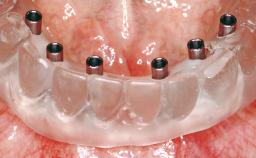

Conventional Loading of Eight Implants in the Maxilla and Final Restoration with a Full-Arch Gold-Ceramic FDP

A 35-year-old Caucasian female presenting with advanced periodontal disease involving both the maxillary and the mandibular dentition was referred for evaluation. The patient, a non-smoker in good general health, requested treatment for recurrent periodontal abscesses, tooth mobility, and discomfort during chewing, as well as restoration of her missing teeth with a fixed prosthesis to improve mastication and esthetics. All residual maxillary teeth exhibited plaque deposits, deep pockets, bleeding on probing, and class III mobility and were evaluated as hopeless. All residual mandibular teeth except tooth 37 could be maintained after periodontal therapy.

# of Implants 8

Prosthesis Type FDP